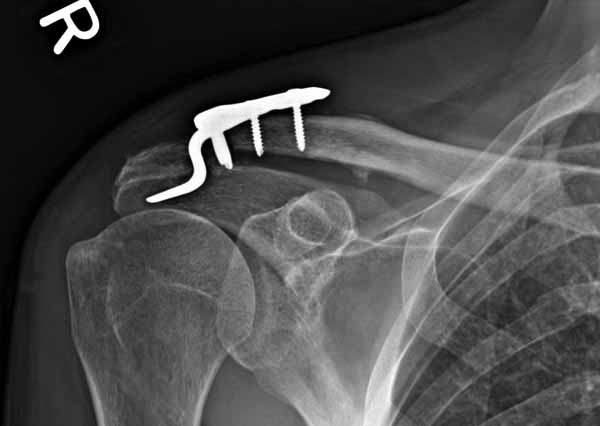

Я ставил польскую http://www.chm.pl/pliki/9878cd2387f303265ebad595b2519dce.pdf, но у них еще не опубликована методика

Но это не помешало успешно пациента прооперировать.

1.JPG

Замечание понял, спасибо и нормальные рентгенограммы, молодец!

Во вторых, это хорошо что нашли длинную пластину, я об этом писал "пластина короткая, не покрывает медиальный диафизарный фрагмент ключицы", и у нас не получилось, пластина не выдержала...

На конференции EFORT в Копенгагене поднимался вопрос о пластинах для остеосинтеза ключицы с крючком. Не имею возможность осветить все что там услышал. Но у меня появилось понимание о импиджмент синдроме, о необходимой длине крючка, о правильном позиционировании пластины, о лизисе акромиона и т.д.

Мне кажется что если понять принципы, то можно использовать и короткую пластину. Что мы с успехом применяли раньше и применяем сейчас, но уже более осознанно. В вашем случае Серж, у меня стойкое ощущение, что необходима дополнительная иммобилизация, так как неправильно выбрано место введения крючка и при ранней нагрузке пластину просто вырвет. Если вам несложно не могли бы вы продемонстрировать прямую и боковую проекцию и в более хорошем качестве. ИМХО

На чем у Вас обосновано" стойкое ощущение, что необходима дополнительная иммобилизация, так как неправильно выбрано место введения крючка"?

Теоретически можно использовать и короткую пластину. Но на операции дистальный отломок( акромиальный конец ключицы ) был коротким и оскольчатым, поэтому крючок и использование там блокированных винтов в пластине было очень уместно. Доступ - "сабельный удар". Точка введения крючка - сразу сзади от ключично-акромиального сустава. Если честно - больше внимания уделяли репозиции отломков и адекватному расположению пластины на ключице :-) крючок проверяли на прочность фиксации за акромион и полный объем движений в плечевом суставе. После операции рука на косынке, нагрузку ограничили. Снимки есть в нормальном разрешении, но здесь "размер файла не превышал 75 кб." Если есть необходимость залью в пикассу...